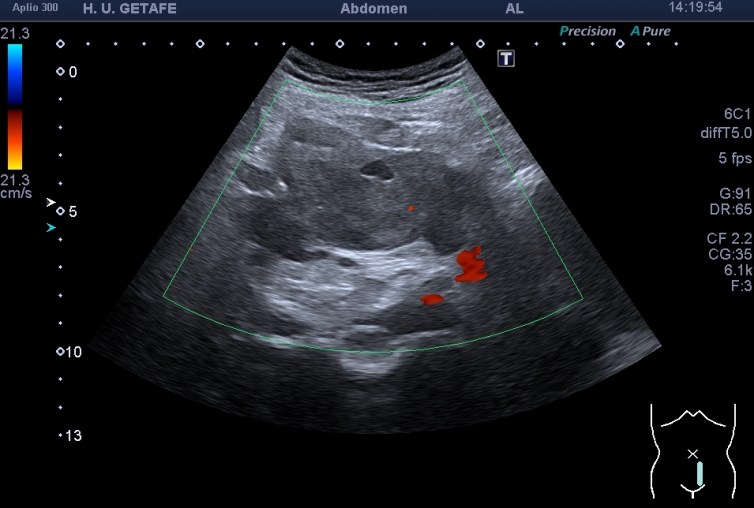

Con la sonda convexa exploré la región pélvica. Masa hipogénica heterogénea,(posibles zonas de necrosis), de contornos lobulados y mal definidos, de aspecto infiltrativo, centrada en el mesosigma. La lesión no depende del sigma, pero está pegada a ella.